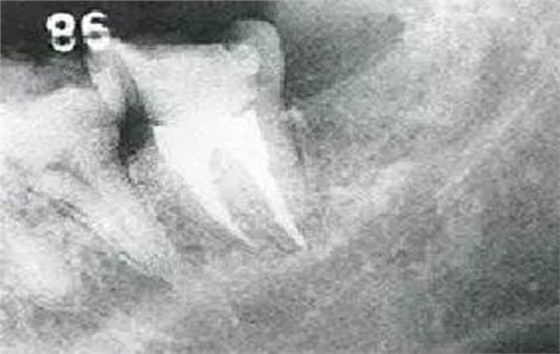

●33歲男性 侵襲性牙周炎廣泛型口腔內(nèi)照片

33歲男性,吸煙(1天10根,12年吸煙史)。菌斑控制狀況不好,牙周探診全頜牙周袋深5~10mm之外,全頜性牙周袋出血,部分牙周袋有排膿現(xiàn)象。X片可觀察到全頜性重度骨吸收。通過(guò)以上檢查可診斷出該患者為侵襲性牙周炎廣泛型。視診可知牙齦雖然有炎癥,但沒(méi)有出現(xiàn)嚴(yán)重浮腫,沒(méi)有大量牙結(jié)石沉積。